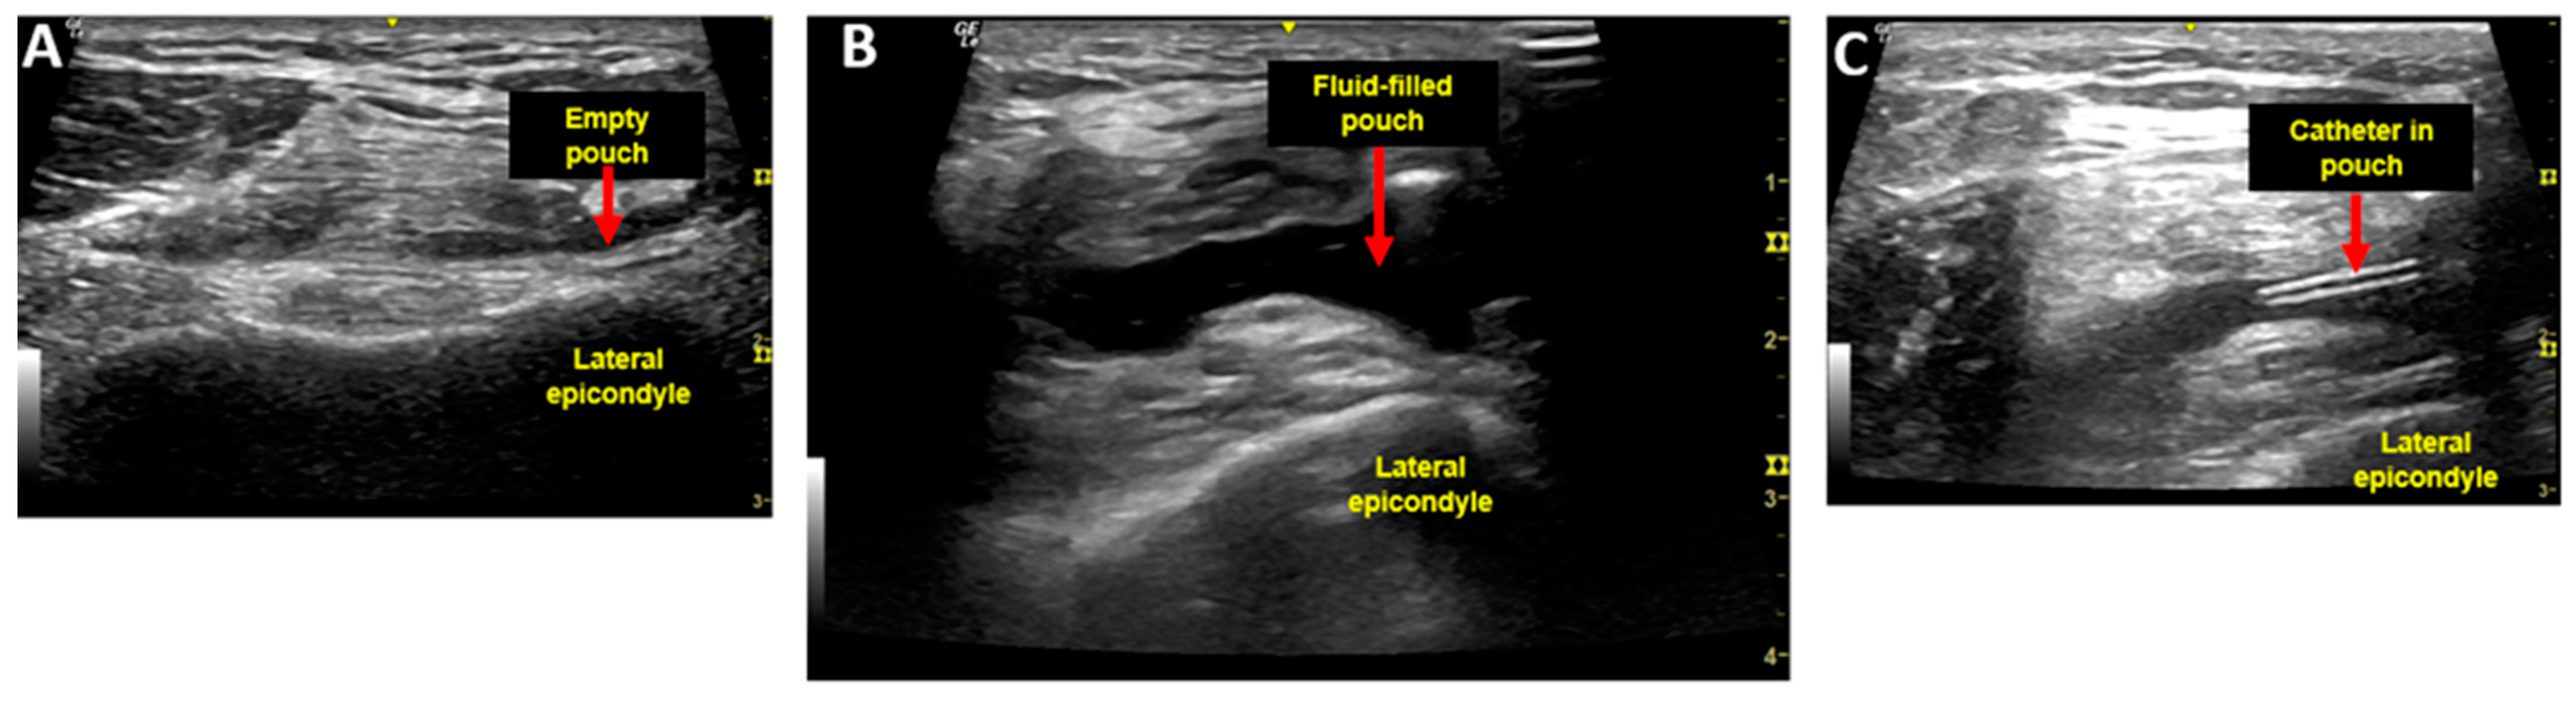

2.1. Injection Procedure and Injectate

2.2. Aspiration Procedure